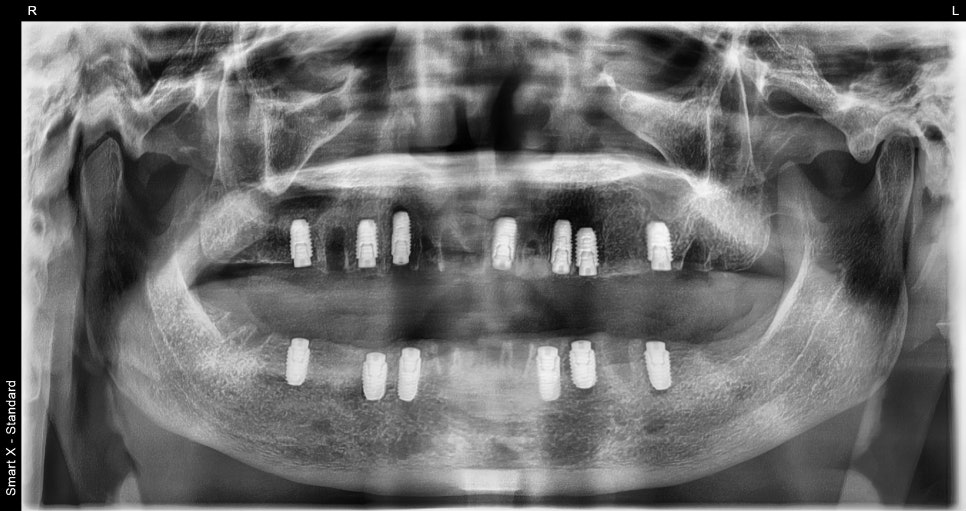

The full-mouth surgery included tooth extraction, bone grafting, sinus lifting,

and placement of all 13 full-mouth implants,

and it was completed in about 2 hours under sedation.

The most important part of the surgery was the position and angle of the molar implants.

Because the molars are a key area that supports the overall bite,

the surgery was performed while maintaining the correct depth and angle

so that chewing force could be distributed naturally.

After placement, the front teeth and molars came together in a balanced way,

restoring a bite that allowed the patient to fully feel the texture of food.